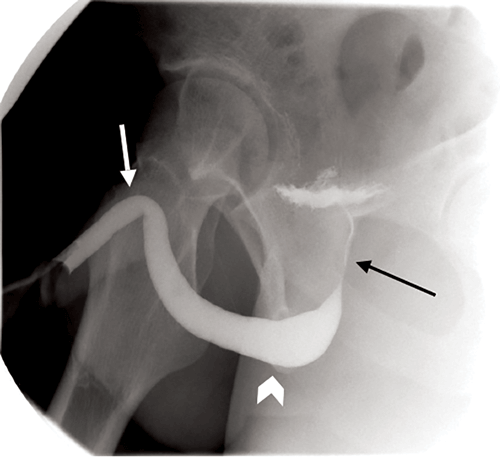

A normal urethrogram should demonstrate a well opacified, smooth and regular urethra. Sometimes contrast will reach the bladder, however this is not essential (Figure 1).

Figure 1: Normal urethrogram with good contrast opacification of the urethra and early contrast within the bladder. Penile urethra (white arrow), bulbous urethra (arrowhead) and prostatic urethra (black arrow).